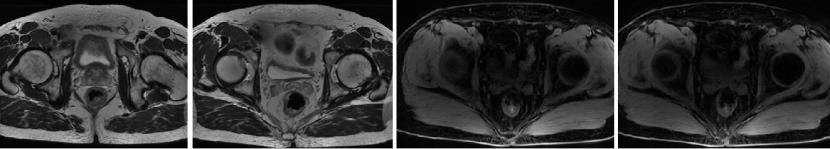

直肠MR增强+DWI:直肠距肛缘约5.5cm处肠壁明显不均匀增厚,累及长度约6.0cm,呈等/长T1、等/稍长T2信号,T2压脂呈不均匀高信号,DWI呈高信号,ADC图信号减低,增强扫描呈明显不均匀强化,相应局部管腔狭窄,邻近浆膜面模糊,周缘可见小淋巴结。

2022-06-12